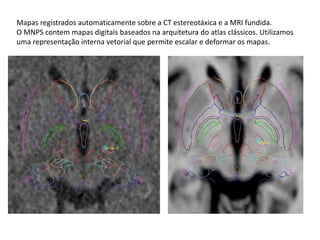

Mapas registrados automaticamente sobre a CT estereotáxica e a MRI fundida.

O MNPS contem mapas digitais baseados na arquitetura do atlas clássicos. Utilizamos

uma representação interna vetorial que permite escalar e deformar os mapas.